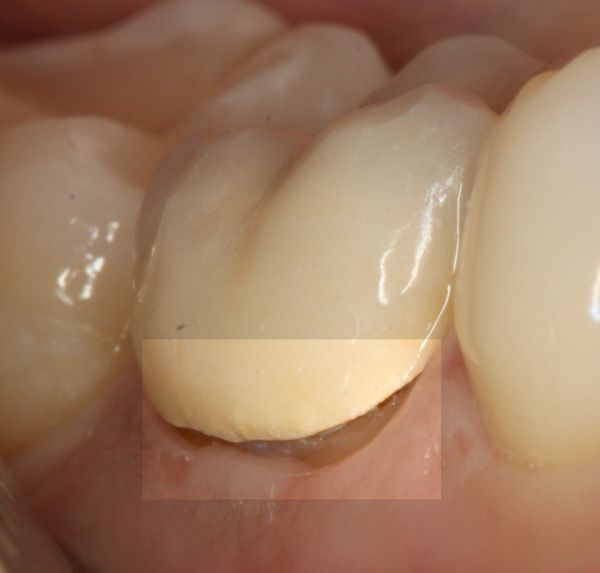

- Σε επόμενη συνεδρία πραγματοποιείται η αποκατάσταση του δοντιού, η οποία πραγματοποιείται με λευκό σφράγισμα ρητίνης ή με στεφάνη (θήκη δοντιού), ανάλογα πάντα με την έκταση της οδοντικής βλάβης.

Όσον αφορά την τελική αποκατάσταση του δοντιού με λευκό σφράγισμα ή θήκη δοντιού, αυτή πραγματοποιείται σε δεύτερη φάση, εφόσον είναι σίγουρο οτι το δόντι παραμένει ασυμπτωματικό.

Καταρχάς θα πρέπει να ξεκαθαριστεί οτι δεν είναι απαραίτητο όλα τα απονευρωμένα δόντια να προστατευτούν με θήκη / στεφάνη δοντιού. Η θήκη είναι απαραίτητη όταν λείπει μεγάλο τμήμα του δοντιού (λόγω τερηδόνας ή κατάγματος) και μετά την ενδοδοντική θεραπεία (απονεύρωση) είναι αναγκαίο το δόντι να προστατευτεί με θήκη για να αποκατασταθεί η σωστή λειτουργία του δοντιού μέσα στο στόμα του ασθενή. Σε περιπτώσεις ακόμη μεγαλύτερων οδοντικών ελλειμμάτων προτείνεται και η τοποθέτηση ενός άξονα, όχι για να “κάνει το δόντι πιο δυνατό” αλλά για να μπορέσει να πραγματοποιηθεί η ανασύσταση του δοντιού και να τοποθετηθεί στη συνέχεια η θήκη από επάνω για την πλήρη προστασία του δοντιού. Αν το δόντι δεν είναι πολύ κατεστραμμένο, τότε η αποκατάσταση του μπορεί να γίνει και με ένα απλό λευκό σφράγισμα δοντιού.

Γιατί μαυρίζει ένα μπροστινό δόντι μετά από απονεύρωση; Πως μπορεί να αντιμετωπιστεί;

Πολλές φορές οι ασθενείς αναφέρουν οτι το μπροστινό τους δόντι μαύρισε μετά από το πέρας της ενδοδοντικής θεραπείας. Πράγματι κάτι τέτοιο είναι πιθανόν να συμβεί, εφόσον υπολείμματα γουταπέρκας (υλικό έμφραξης των ριζών του δοντιού) στη μύλη του δοντιού μπορούν να προκαλέσουν τον αποχρωματισμό / “μαύρισμα” του δοντιού. Είναι σημαντικό λοιπόν όταν ο οδοντίατρος πραγματοποιεί την απονεύρωση να καθαρίζει πολύ καλά και να μην αφήνει υπολείμματα γουταπέρκας στο μύλη του δοντιού. Σε περίπτωση που πράγματι μαυρίσει ένα πρόσθιο δόντι ο ενδοδοντολόγος μπορεί να το διορθώσει και να επαναφέρει το αρχικό όμορφο λευκό χρώμα του δοντιού. Η διαδικασία είναι απλή και πραγματοποιείται με εσωτερική λεύκανση του εν λόγω δοντιού. Αν το δόντι δεν “ανοίγει “ χρωματικά τότε για αισθητικούς λόγους μπορεί να πραγματοποιηθεί όψη ή θήκη δοντιού.